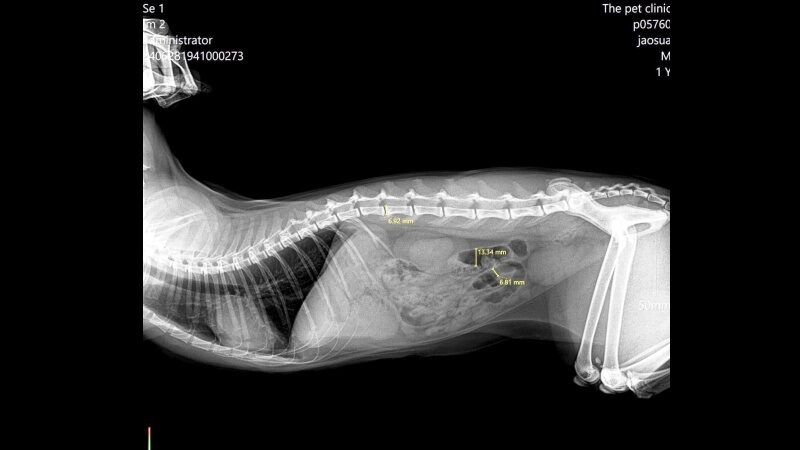

"โดยน้องแมวกลืนลูกปอม ๆ ไป 4-6 เม็ด จากนั้นมีการอาเจียนออกมา เรารีบพาน้องไปพบคุณหมอ รวมถึงตรวจเลือดและเอกซเรย์ คุณหมอแจ้งว่า ลูกบอลเป็นวัตถุที่ไม่สามารถเห็นผ่านฟิล์มภาพได้ ต้องทำการกลืนแป้ง แต่มีเอฟเฟกต์ เพราะแมวบางตัวอาจจะต่อต้าน แนะนำให้ดูอาการ ถ้าน้องมีอาการอาเจียนหรืออึไม่ออก อาจจะต้องใช้วิธีนี้ เพราะถ้าปล่อยไว้ลูกบอลจะไปอุดตันลำไส้อาจจะต้องผ่า"**